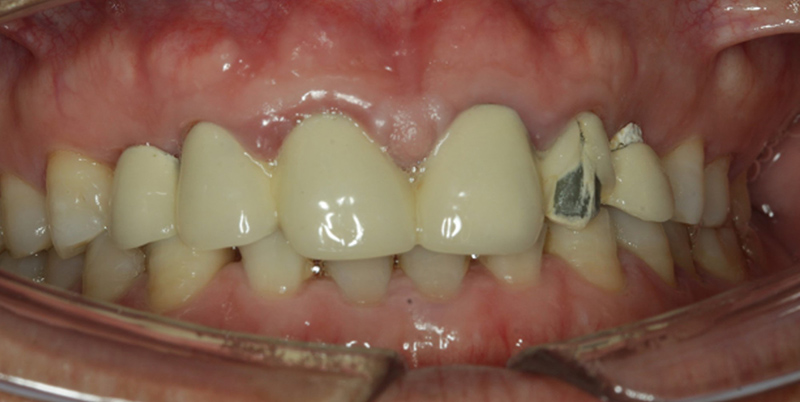

主訴:前牙烤瓷冠損壞,要求種植修復(fù)

現(xiàn)病史:左側(cè)烤瓷牙崩瓷,影響美觀

檢查:22烤瓷牙表面崩瓷,13、23、24缺失

診斷:患者13、23、24缺失,上頜竇囊腫明顯,23、24頰側(cè)牙槽骨吸收嚴(yán)重

1、不良修復(fù)體松動(dòng)脫落,崩瓷;

2、深覆合;

3、牙齦炎。